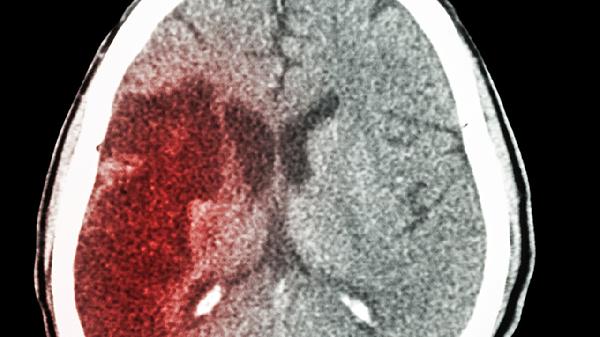

脑梗这个"隐形杀手"总是来得悄无声息?别以为只有剧烈头痛才是警.报!最新医学观察显示,近60%的脑梗患者在发病前都出现过一些容易被忽视的身体信号。这些预警往往伪装成普通小毛病,却可能救你一命。